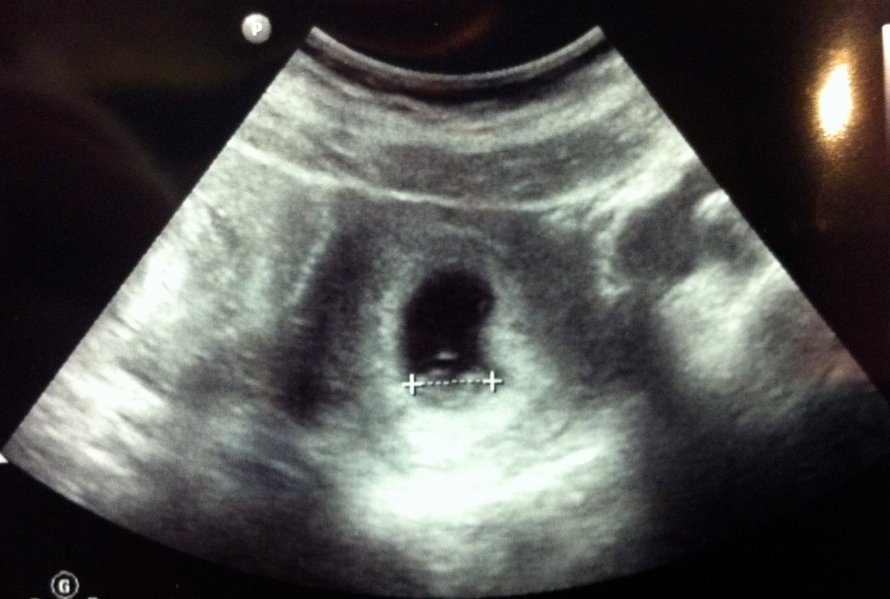

A week later I had my first prenatal appointment. It’s amazing the midwife could just touch my belly and know that I was 6 weeks along. Phuuuuf…in my mind I was just given an extra 5 weeks to comprehend our new life and embrace it. Just to make sure she was right, the she did an ultrasound…and it was at that very moment that I truly became a mommy. Right there, the size of a sesame seed, was our baby…heart beating like a hummingbird and moving around like a jumping bean. All I could do was laugh…excited, nervous, and in total awe at the miracle of life.